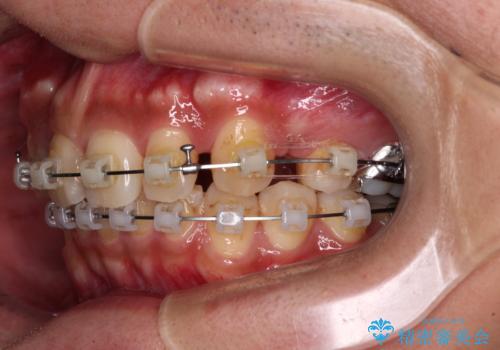

【モニター】八重歯と正中のずれた歯列 片顎抜歯のワイヤー矯正

- クリアブラケット

- 上顎の八重歯と正中のズレを気にして来院された患者様です。

八重歯による叢生は著しく、それにより上顎の正中が大きく右にずれている状態でした。

口元の突出感は感じていなかったことと、奥歯の咬み合わせを考慮し、上顎のみ左右の第一小臼歯を抜歯してワイヤー装置にて矯正治療を行うこととしました。

補助装置を併用することで効率的に八重歯や正中位置の改善を達成することができました。